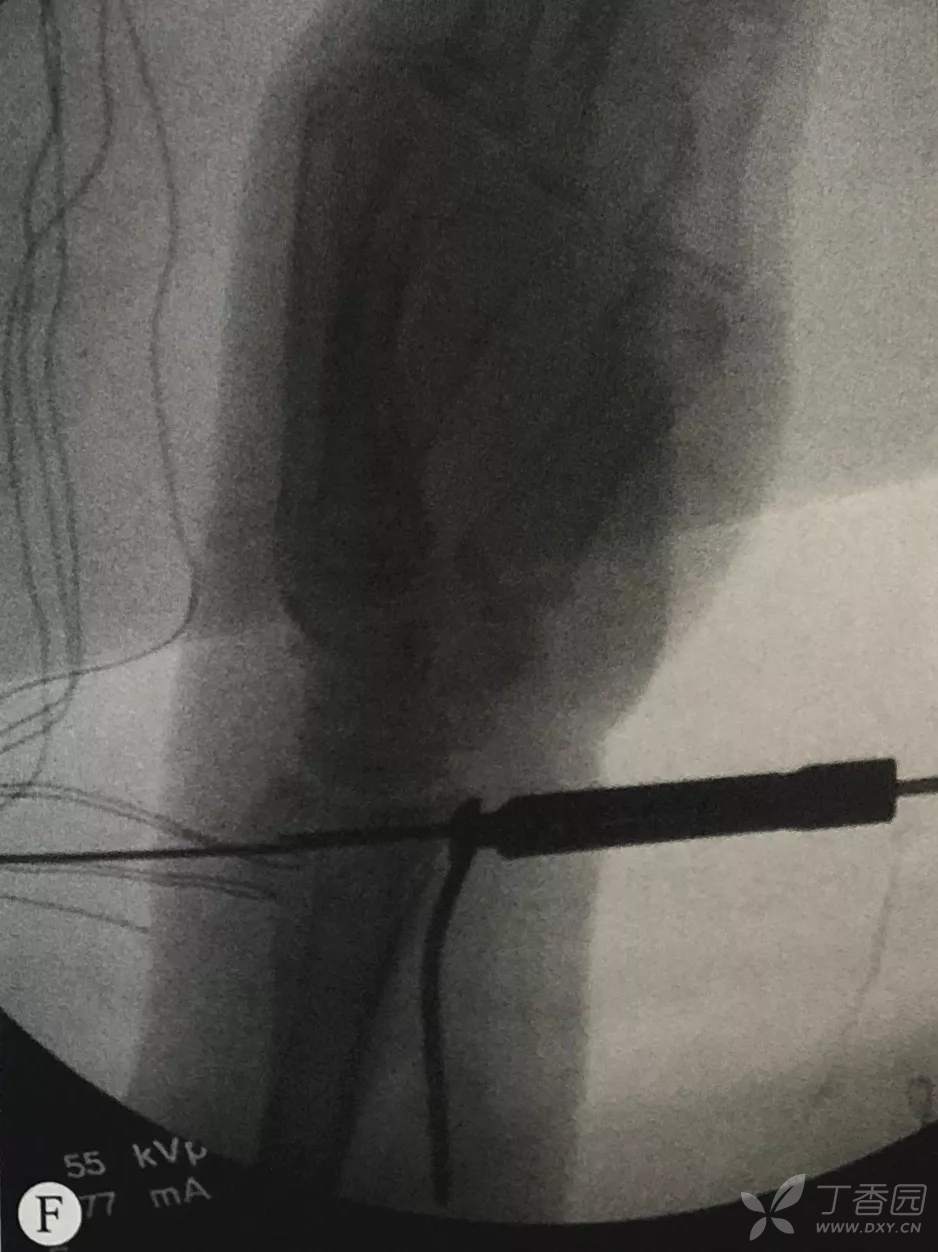

- 患者仰卧位,患肢外展置于床旁可透视托架上;

- C形臂术中透视。